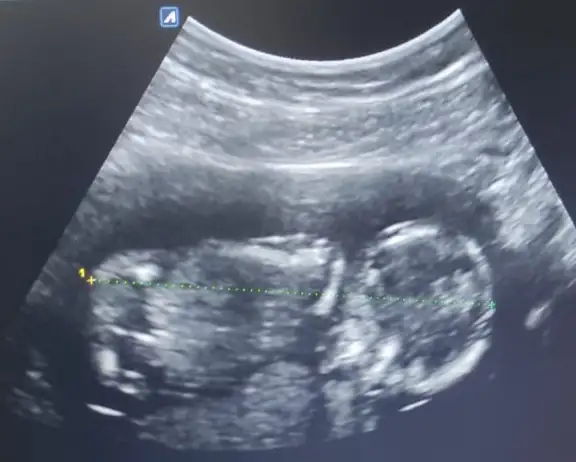

Kese uzunsa erkek yuvarlaksa kız mi ?

Banana bakarmisiniz

Kızlar bı arkadaş keseye göre tahmin yapıyor ve hep tutuyormuş iki oğlunu da bu şekilde cok yeniyken bile tahmin etmiş...ogullarinda kesesi hep uzunmuş muz gibi...yuvarlak ve yuvarlağa yakın olanlar hep kızdır diyor..ve bayağı emin konusuyor..benimki şişman bı fasulye gibi oo kesin kız görürsün dedi...sizlerin keselerinin şekli nasıldı ve cinsiyet neydi konusalimmi 😊